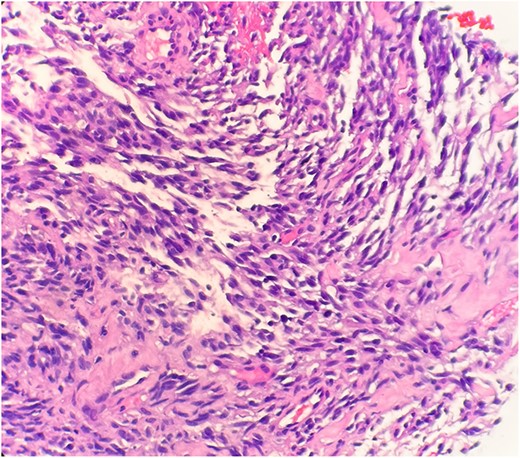

The pathological sections taken from the mass demonstrated spindle-tumor cells within a focal sclerotic and myxoid stroma with increased mitotic activity; no necrosis was visualized (Fig. 1). The vessels from the pleural mass showed a staghorn-like appearance. Tumor cells biopsied from the lung mass were positive for vimentin and CD10, as well as biomarkers for sarcomatoid mesothelioma: WT1 and D2–40 (Fig. 2). The tissue sample was negative for immunostains keratin and calretinin, which is unusual for mesothelioma. The lung mass biopsy was also negative for cytokeratin (CK) and PAX8, which ruled out the possibility of metastatic RCC. Due to the visualization of staghorn-appearing vessels, malignant solitary fibrous mesenchymal tumor was considered as well but was ruled out due to lack of STAT6 expression.

Microscopic examination reveals spindle tumor cells in sclerotic and myxoid stroma (HE stain x40).